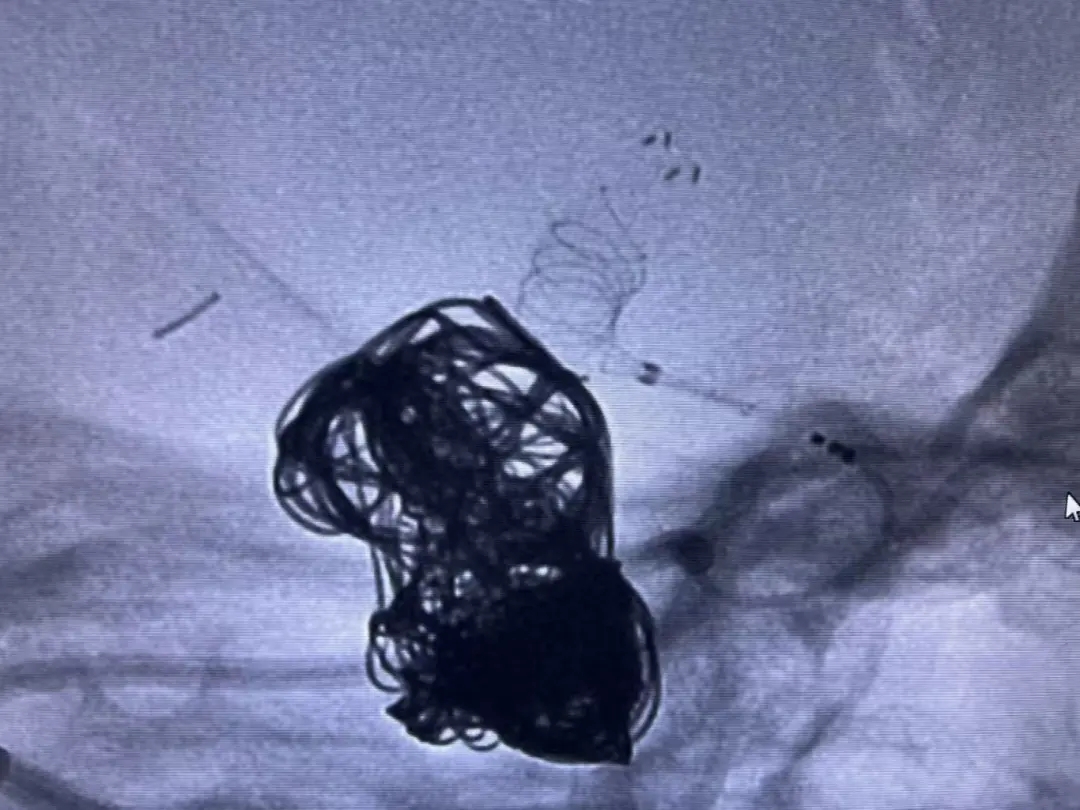

手术在全身麻醉下进行。医生成功穿刺右侧桡动脉,精准植入密网支架。整个过程非常顺利,支架位置理想,完美覆盖动脉瘤并保护了正常血管分支。

术后影像显示,动脉瘤内血流明显受阻,手术效果立竿见影。患者恢复良好,具体表现为:无任何神经系统并发症; 穿刺部位无异常;术后24小时即可正常活动。